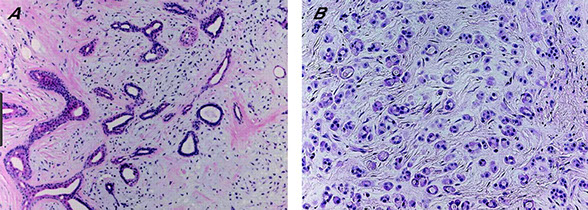

Trichoblastoma

An adnexal tumor made of ribbons of basaloid cells with basaloid islands, clefts bwt collagen, concentric fibroblastic rich stroma with no retraction

Micro: cells can look a lot like BCC, but the stroma has concentric fibroblast-rich collagen

- papillary mesenchymal bodies can be in the stroma, but mucin will never be in stroma (mucin only within tumor islands)

Lymphadenoma

- aka adamantinoid trichoblastoma

Variant of trichoblastoma with blue tumor islands that have up to 2 layers of peripheral basal cells

- center of the islands are pale due to clear cells and inflammatory cells (lymphocytes and histiocytes)

- fibroblast-rich stroma with no retraction

Tx/Px: B9, just needs F/U

Cutaneous lymphadenoma